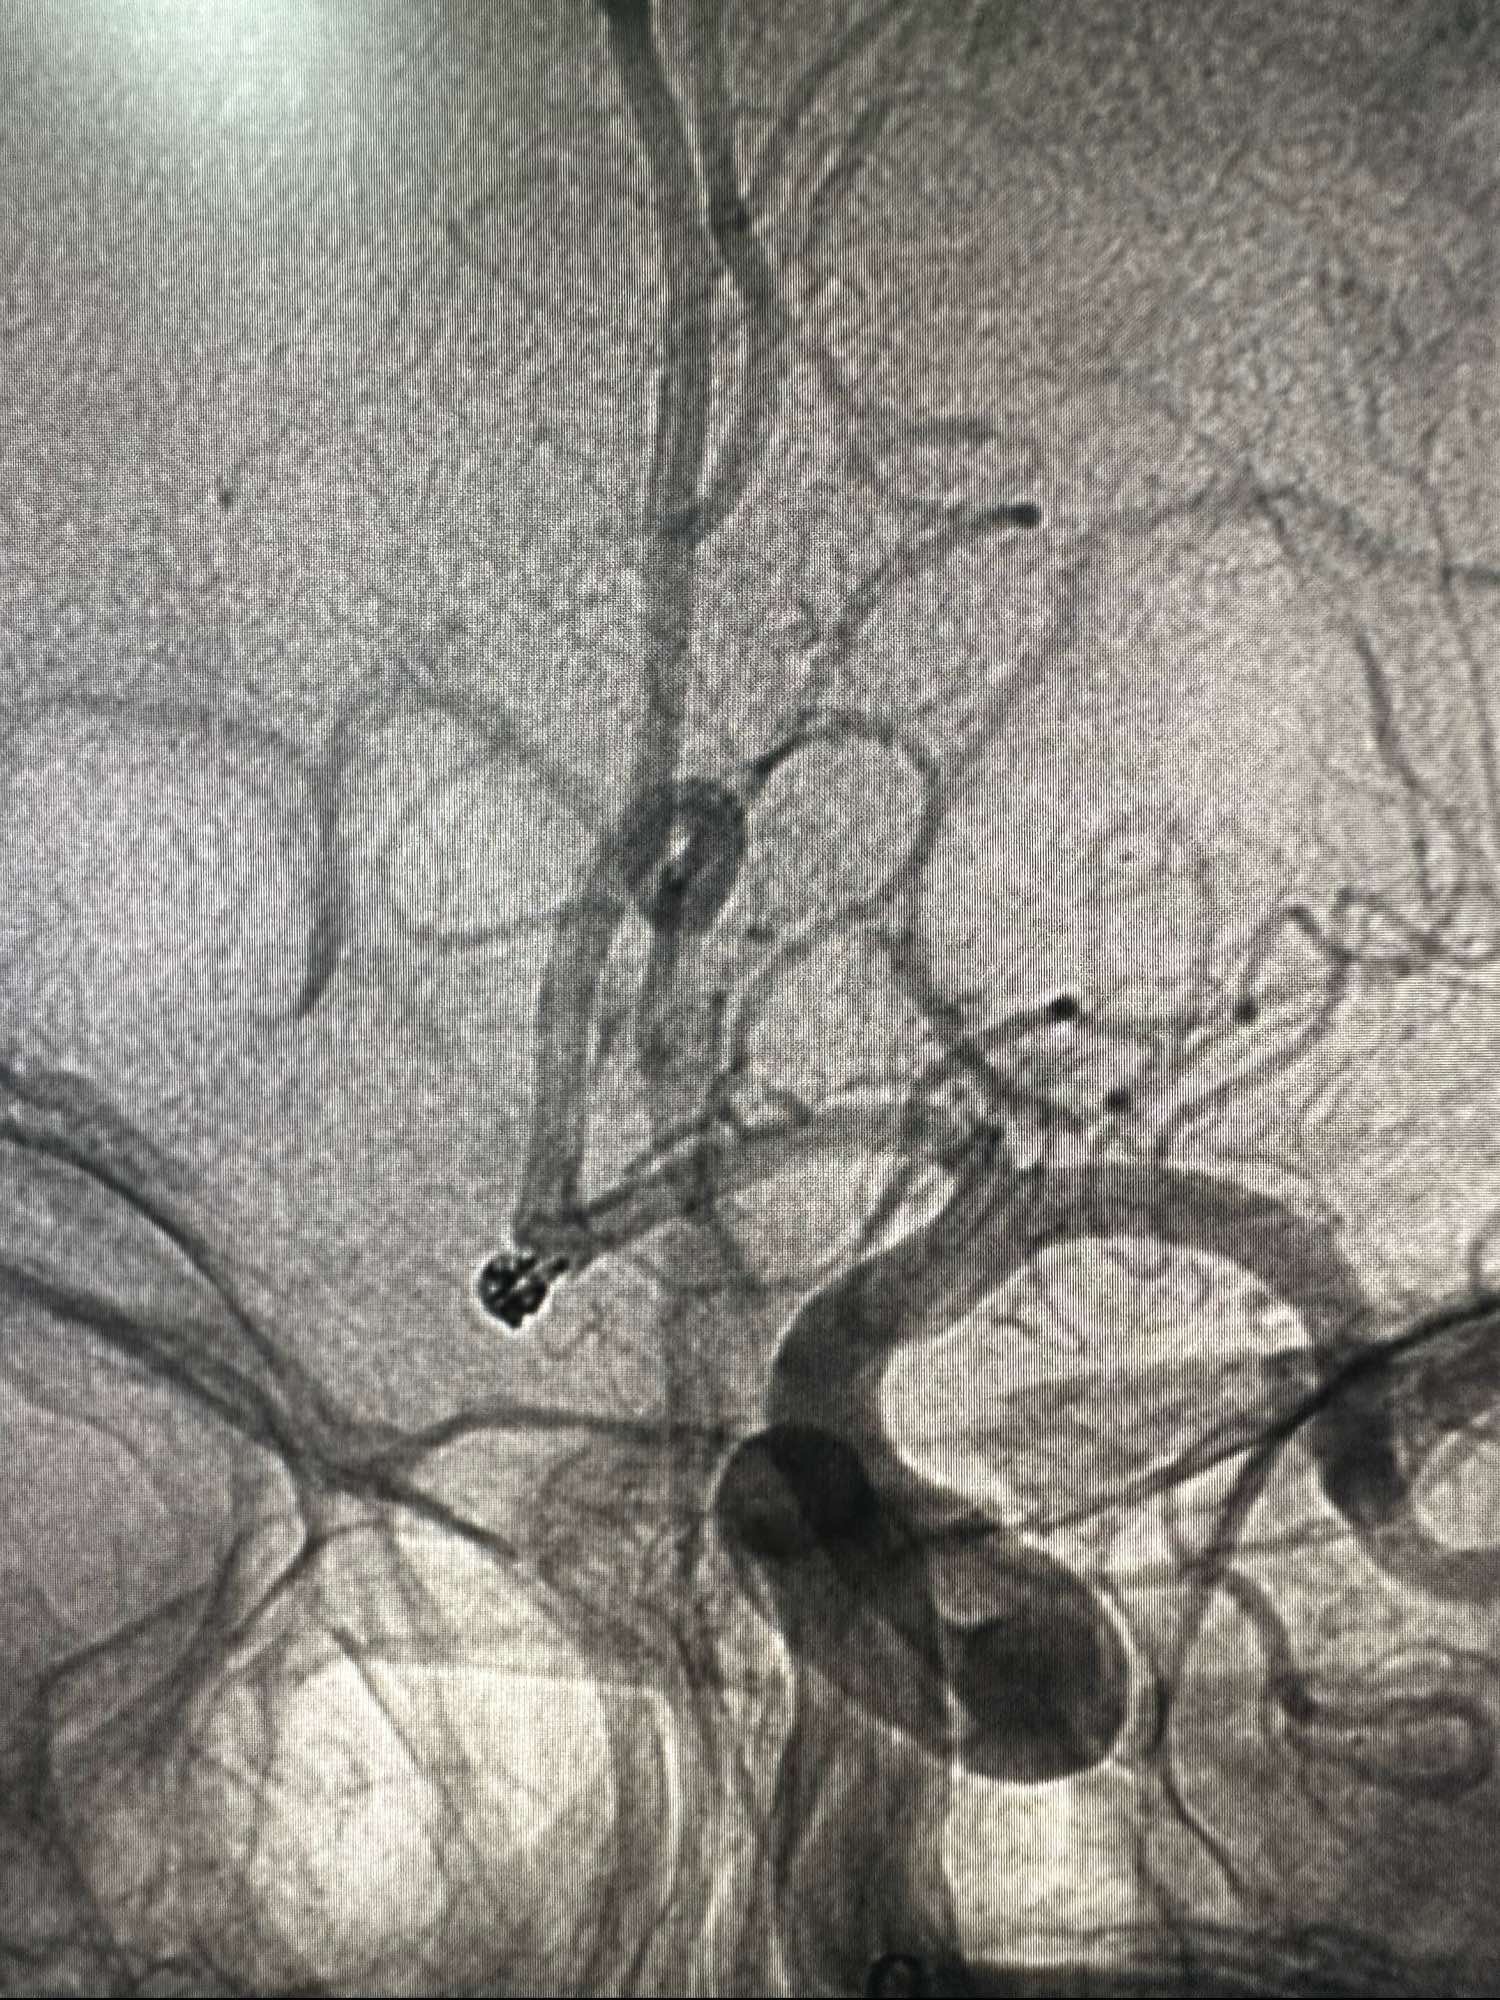

另外一个角度